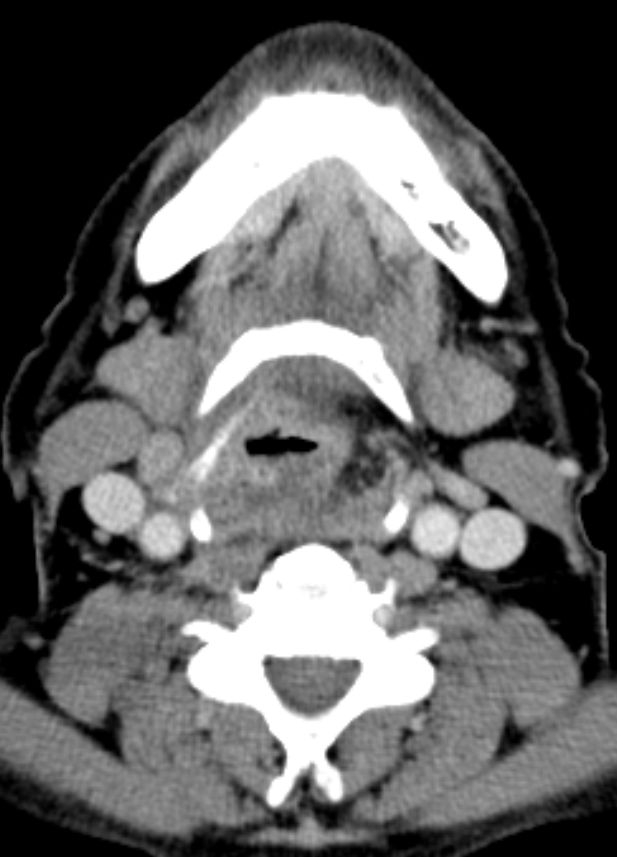

Lymphknotenrezidiv 2 Jahre nach Cordektomie.![]() |